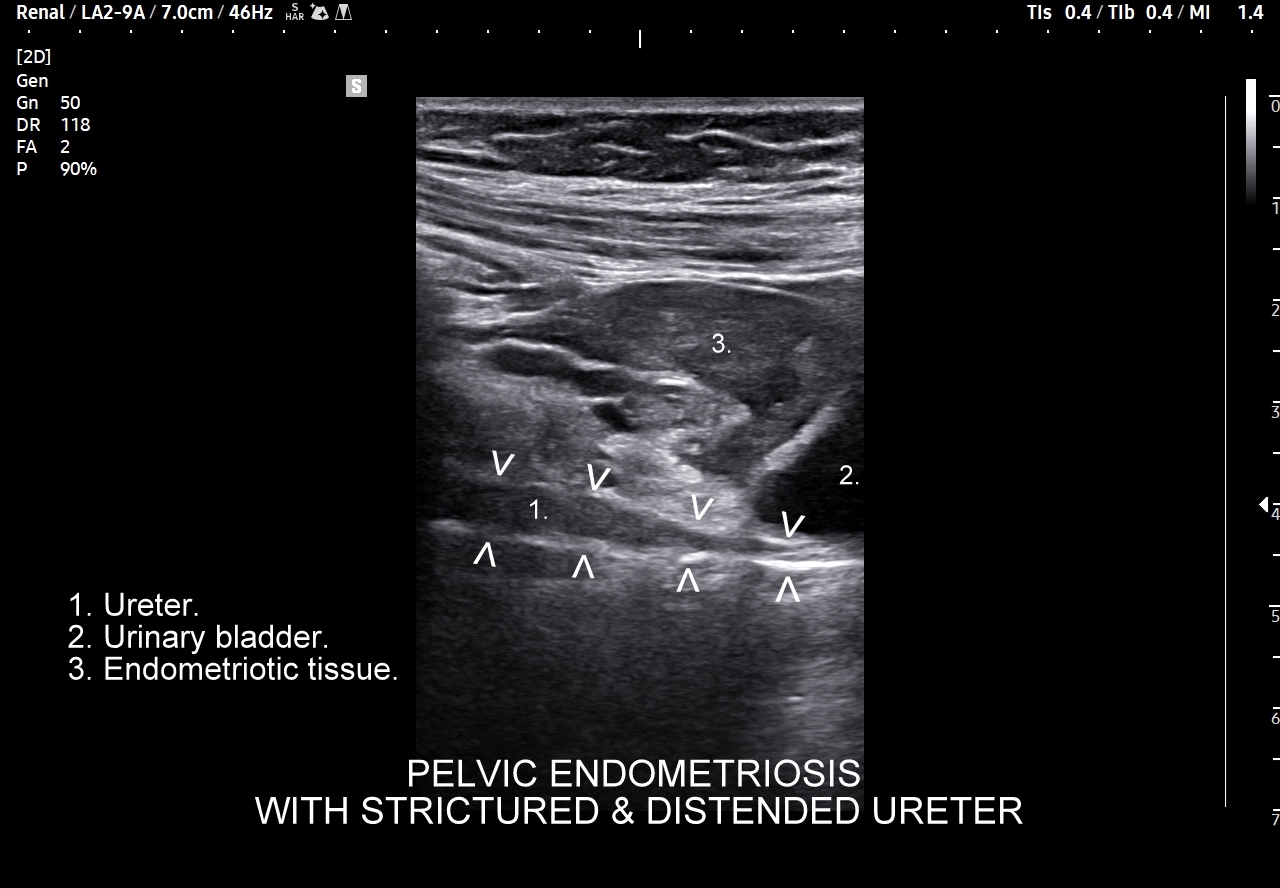

W badaniu USG ogniska endometriozy zwykle przyjmują formę hypoechogennych guzków i nieregularnych mas; mogą być niejednorodne echogenicznie i zawierać drobne obszary torbielowate; w trybie color-Doppler i MVI wykazują skąpe unaczynienie.

Na skanach w niniejszym artykule zaprezentowany jest przypadek endometriozy głębokiej w miednicy mniejszej z intraluminalnym nacieczeniem dystalnego odcinka moczowodu, jego całkowitą niedrożnością i wtórnym wodonerczem. Choroba w tak zaawansowanym stadium wykryta została przypadkowo w rutynowym przezbrzusznym badaniu USG jamy brzusznej. W ramach diagnostyki różnicowej przeprowadzone zostały badanie CT, MRI oraz ureterocystoskopia z pobraniem materiału do badania histopatologicznego, na podstawie którego postawiono rozpoznanie endometriozy.